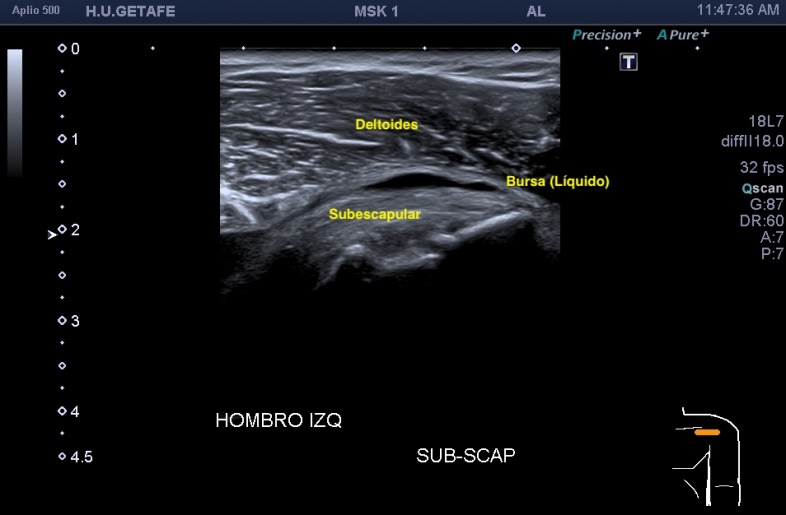

2.Tendón del subescapular

El tendón de subescapular es una estructura que no debe ir rodeada de líquido, por experiencia, cuando la presencia de líquido es evidente en esta localización, sabemos que la exploración depara alguna sorpresa más adelante en relación con rotura en algún tendón de más o menos envergadura.

Imagen superior, normalidad, imagen inferior, patología entre el deltoides y el subescapular. Te recomiendo encarecidamente la realización de la dinámica de este tendón, bajo la coracoides, donde desliza el subescapular, puede esconderse la bursa con líquido en la aducción que se revela visible en la abducción forzada, para el estudio de este tendón.